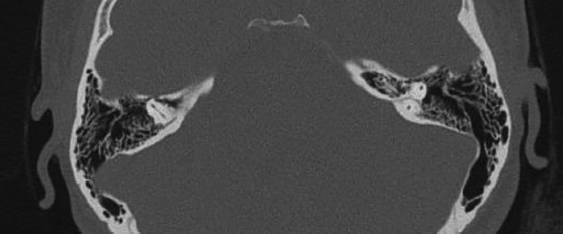

기저질환이 없는 24세 여환이 1년 전부터 발생한 우측 이명을 주소로 내원하였다. 이명은 박동성으로 심장박동과 일치하였으며 밤에 조용하게 누워있을 때, 고개를 왼쪽으로 돌릴 때 커지는 양상이었다. 환자의 측두골 전산화단층촬영 검사결과는 다음과 같다. 이 질환에 대한 설명으로 옳은 것은?

해 설 우측 S자 정맥 피열(sigmoid sinus dehiscence)에 연관된 혈관성 이명 증례이다. 혈관성 이명은 반드시 환자의 심장 박동과 일치하는 이명이어야 하며, 저음역이명에 의한 차폐 효과로 저음역에 가성 감각신경성 난청이 관찰되기도 한다. 병변측 경정맥 부위 압박으로 이명이 줄어들거나 소실되고, 고개 회전 시 경정맥 혈류량이 변화하므로 병측으로 회전시 감소, 병변 반대측으로 회전시 이명의 크기가 증가하는 경향을 보인다. 빈혈, 갑상선기능 항진 등 내과적 질환에 의해 악화되므로 감별하여야 하며, 물 폐쇄 검사로 공기 펄스 기전과 와류 전도 기전을 감별하여 치료 방침 결정에 참고한다. 보존적 요법에 반응하지 않는 경우 vascular resurfacing이 가장 일반적인 치료 방법이다.